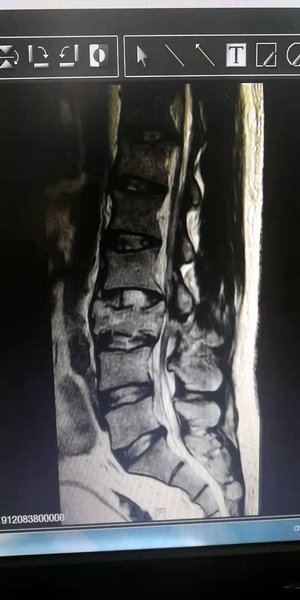

稍后,陶先生被家属送到了附属二院骨外科三病区,经紧急腰椎核磁共振检查后,陶先生的病情与朱剑峰主任的判断完全一致,他腰椎第3椎体爆裂性骨折并压迫神经。明确诊断后,朱剑峰主任立即组织科室医护人员讨论病情、制定手术方案,经缜密分析决定为陶先生实施钉棒内固定术。

陶先生术前核磁影像